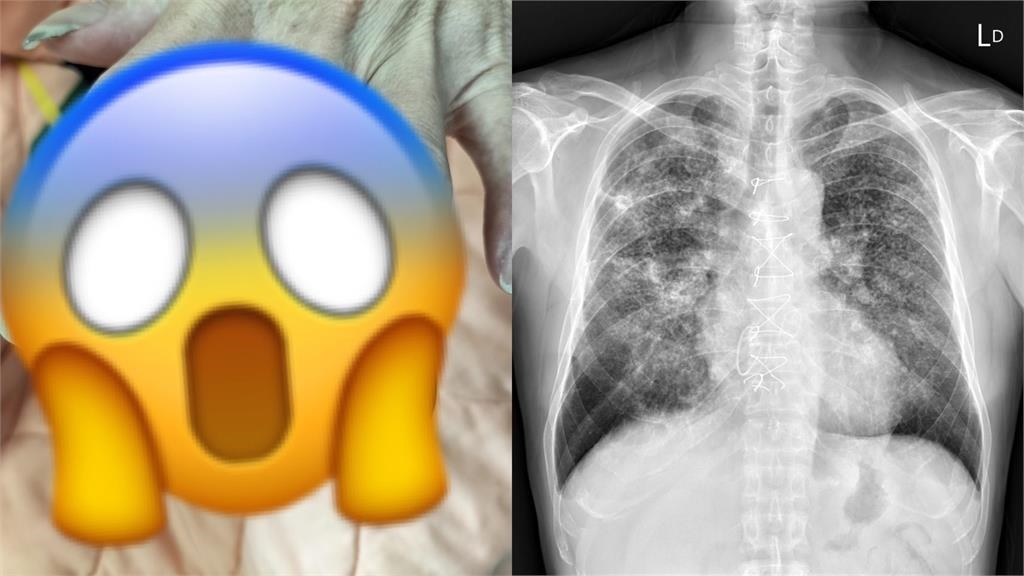

蘇一峰最後也提醒,「看到手指變成杵狀指,記得找醫師檢查一下」。對此,網友見狀也好奇留言詢問「這是什麼病」?而根據衛福部健康署的資料,其實杵狀指並非疾病,而是一種「肢端末梢肥大」的症狀,常造成指甲床跟指節的角度變形。若將雙手十指第一節靠在一起,2個指節的指甲間密合無縫隙的,就可能是所謂的「杵狀指」。

另外,若有杵狀指症狀,可能代表心肺功能或腸胃道功能有問題,且已經造成供氧問題,讓身體長期處於缺氧狀態,雖然有資料指出,出現杵狀指有可能罹患肝癌、肺癌、淋巴癌或心臟相關疾病等,但並非所有的肺癌患者都會出現「杵狀指」或手指密合度異常,因此若察覺身體有異狀時應諮詢醫師,誤以網路資訊自行判斷而延誤就醫。